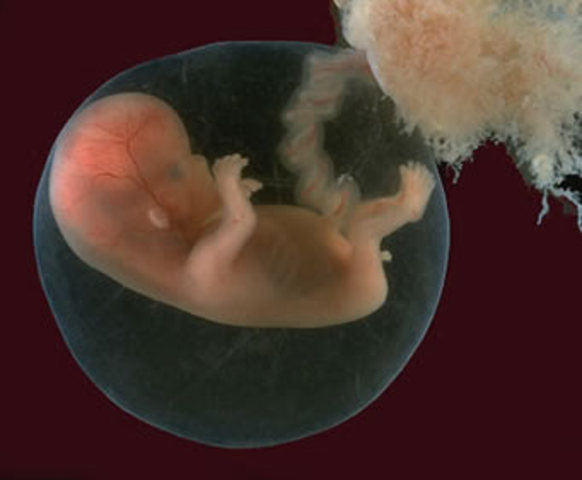

• 9 semanas Características externas

9 semanas Características externas

-El cuello se desarrolla y el mentón se separa del tórax

-La flexión craneal es de cerca de 22 grados

-El corion se divide en liso y frondoso

-Los párpados se encuentran y se fusionan

-Los genitales externos empiezan a mostrar especificidad de género

• 9 semanas. Características internas

9 semanas. Características internas

-Los intestinos se hernian dentro del cordón umbilical

-Se producen los primeros movimientos musculares

-La hipófisis produce ACTH y gonadotropinas

-La suprarrenal produce corticosteroides

-Se completan las válvulas semilunares del corazón

-Los conductos paramesonéfricos fusionados se unen en la placa vaginal

-Los pliegues uretrales comienzan a fusionarse en los varones